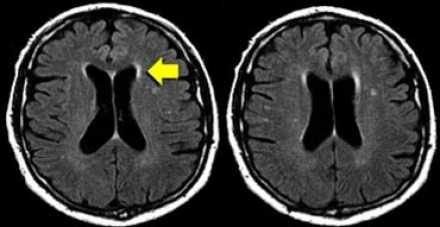

НОРМАЛЬНЫЕ ВОЗРАСТНЫЕ ИЗМЕНЕНИЯ

БЕЛОГО ВЕЩЕСТВА НА МРТ

К ожидаемым возрастным изменениям относятся:

- Перивентрикулярные «шапочки» и «полосы»

- Умеренно выраженная атрофия с расширением борозд и желудочков мозга

- Точечные (и иногда даже диффузные) нарушения нормального сигнала от мозговой ткани в глубоких отделах белого вещества (1-й и 2-й степени по шкале Fazekas)

Перивентрикулярные «шапочки» представляют собой области, дающие гиперинтенсивный сигнал, расположенные вокруг передних и задних рогов боковых желудочков, обусловленные побледнением миелина и расширением периваскулярных пространств. Перивентрикулярные «полосы» или «ободки» это тонкие участки линейной формы, расположенные параллельно телам боковых желудочков, обусловленные субэпендимальным глиозом.

На магнитно-резонансных томограммах продемонстрирована нормальная возрастная картина: расширение борозд, перивентрикулярные «шапочки» (желтая стрелка), «полосы» и точечные очажки в глубоком белом веществе.

Клиническое значение возрастных изменений мозга недостаточно хорошо освещено. Тем не менее, имеется связь между очагами и некоторыми факторами риска возникновения цереброваскулярных расстройств. Одним из самых значительных факторов риска является гипертония, особенно, у пожилых людей.

Степень вовлечения белого вещества в соответствии со шкалой Fazekas:

- Легкая степень – точечные участки, Fazekas 1

- Средняя степень – сливные участки, Fazekas 2 (изменения со стороны глубокого белого вещества могут расцениваться как возрастная норма)

- Тяжелая степень – выраженные сливные участки, Fazekas 3 (всегда являются патологическими)